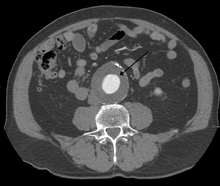

CT reconstruction image of an abdominal aortic aneurysm | |

The diagnosis of an abdominal aortic aneurysm can be confirmed at the bedside by the use of ultrasound. Rupture may be indicated by the presence of free fluid in the abdomen. A contrast-enhanced abdominal CT scan is the best test to diagnose an AAA and guide treatment options.